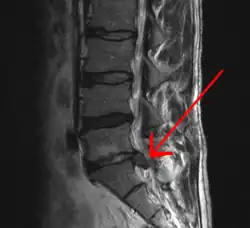

![]() МРТ-изображение межпозвонковой грыжи между сегментом L5 поясничного отдела и крестцом. | |

Межпозвонковая гры́жа (грыжа межпозвонкового диска) — выпячивание (экструзия) ядра межпозвонкового диска в позвоночный канал в результате нарушения целостности фиброзного кольца.

Грыжи относительно редко требуют хирургического вмешательства, тем не менее в США ежегодно проводится более 200 тысяч, а в Германии — 20 тысяч вмешательств. В 48 % случаев грыжи локализуются на уровне L5-S1 пояснично-крестцового отдела, в 46 % случаев — на уровне L4-L5, остальные 6 % — на других уровнях или на нескольких уровнях пояснично-крестцового отдела. Менее тяжёлое состояние — выпячивание ядра межпозвоночного диска без разрыва фиброзного кольца, называется протрузией.

Методом выбора диагностики грыж межпозвонковых дисков в настоящее время является магнитно-резонансная томография (МРТ) или мультиспиральная компьютерная томография (МСКТ). При необходимости проводится неинвазивная МР-миелография или инвазивная КТ-миелография.